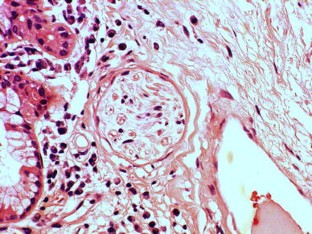

Ionizing radiation as a cancer therapy is associated with a variety of undesirable side effects. Consequently, radiotherapy can negatively affect neuromuscular function. Clinical observations have identified problems with swallowing and voice function. Our study aims to evaluate the impact of radiotherapy on laryngeal soft tissues using image analysis to quantify its effect on the structure of the vocalis and thyroarytenoid muscles. Case control study, retrospective analysis. We collected total laryngectomy specimens from six patients with persistent or recurrent cancer who had received preoperative radiotherapy (60–66 Gy). The control group consisted of total laryngectomy specimens from six patients who underwent surgery as primary treatment. Sampling of the specimens only included non-cancerous laryngeal tissue. Laryngeal histological slices were evaluated using digital morphometric analysis system. Percentage of fibrosis and density of muscle fibers within the thyroarytenoid muscle were evaluated in both groups. We found no significant quantitative differences in muscle fibrosis (7.92% vs. 7.52%, P > 0.1). Changes were rather qualitative and included changes in the organization of the muscular fibers. A significant reduction in muscle fibers, however, was observed in the samples from irradiated larynges (66.45% vs. 42.03%, P < 0.01). Our analysis suggests that radiotherapy is responsible for a significant reduction in muscle fibers in the thyroarytenoid muscle and that these changes occur during treatment or relatively early after its completion. Loss of muscle mass after irradiation correlates with clinical observations of muscle weakness and decreased function in patients who undergo radiotherapy.

Fig. 1